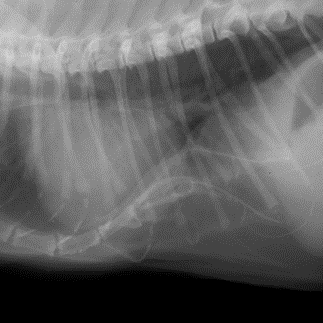

漏斗胸猫小判 レントゲン比較 みこまんまの猫まんま